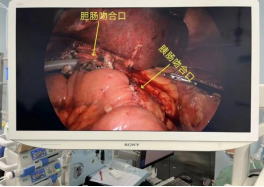

患者金大爷,因梗阻性黄疸到我院就诊收住消化内科,完善相关检查后发现胆管占位性病变 ,胆总管下段壁稍增厚,低位胆道梗阻待鉴别;腹腔内及腹膜后淋巴结增多部分稍增大;肝脏多发囊性病变待排;胆囊稍肿大并胆汁浓缩。经院内会诊后,患者转入普外二科继续下一步治疗。我院普外二科主任李国松向患者及家属详细讲解病情的复杂性和手术的必要性,在排外手术禁忌后,拟定了高难度的手术方案——腹腔镜下胰十二指肠切除术+肝病损切除术+胆囊切除术。 在做好充分术前准备的基础上,普外二科手术团队披上“绿战袍”,向腹部手术的“珠穆朗玛峰”发起挑战。

在手术室麻醉团队和护理团队的配合下,历时8小时41分钟,手术取得成功。医护团队默契配合、精准操作,术中出血量仅为200ml,术后患者麻醉苏醒后安返病房。在全体医护人员的精心治疗和护理下患者恢复良好顺利出院。